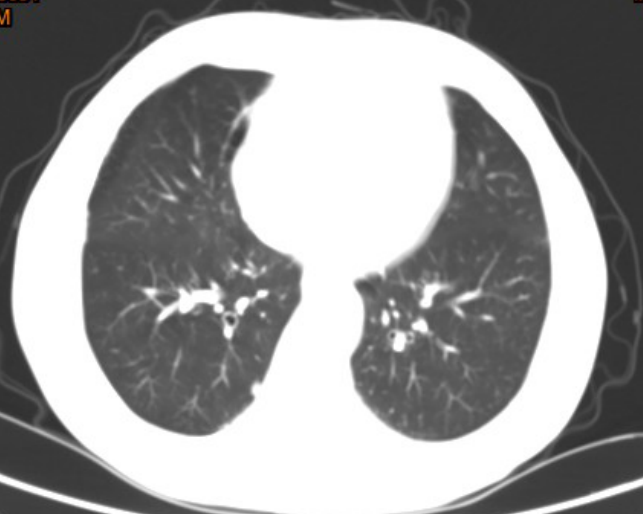

影像学检查

左肺上叶结节影,边界光整,大小约11*12mm,两肺见多发大小不等结节灶。

手术所见:胸腔镜下行肺叶部分(左肺上叶结节)切除术,术中探查见肿块约2*1.5*1cm大小,位于前段与舌段交界处。